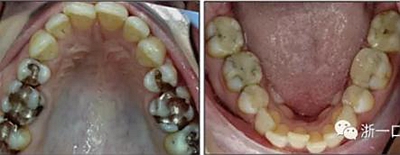

患者曾行正畸治療,現覺笑容不美觀前來就診?;颊哒嬗^及側貌示下頜發(fā)育不足,偏高角,唇閉合不全。上下頜中線齊。覆合、覆蓋4毫米。磨牙關系及尖牙關系II類。上頜擁擠度4mm,下頜擁擠度6mm。4顆第一前磨牙在第一次正畸治療時已拔除。上下牙弓呈尖圓型,牙弓狹窄。

由于下頜中切牙間沒有間隙行下頜正中切開術,故進行術前正畸擴展間隙。下頜前牙粘托槽,中切牙托槽成交放置,將中切牙牙根分開。使用0.018X0.018鎳鈦絲及置于下頜左、右中切牙之間的推簧推間隙。3個月后拍攝CBCT示已有足夠間隙行下頜正中截骨術。

擴弓保持8周后,除擴弓器影響牙外粘接托槽,使用0.014鎳鈦絲進行排齊、整平。旋轉停止后3個月拆除擴弓器,全口粘接托槽,使用0.016niti繼續(xù)排齊整平。佩戴可摘保持器,保持上頜寬度。在使用至0.018x0.018niti7周,徹底排齊整平后,使用大弓型的0.016x0.022不銹鋼絲,繼續(xù)維持原有寬度,同時停止使用可摘保持器。掛II類牽,糾正磨牙關系,使用鏈圈關閉散在間隙,少量使用IPR去除局部前牙的黑三角。術后9個月拍全景示,牙根平行度可,再無其他牙根出現問題。1年7個月后治療結束。上下頜3-3舌側保持器+哈雷氏保持器進行保持。